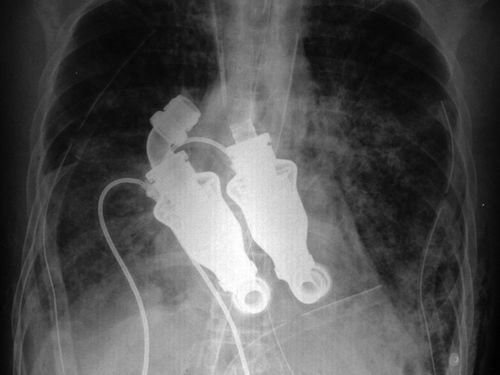

取代心脏的离心泵是一个类似涡轮的装置,装有结构简单的涡动转子。

取代心脏的离心泵是一个类似涡轮的装置,装有结构简单的涡动转子,由科赫和弗拉泽尔研制。它并不会像心脏一样跳动,而是像花园的水管一样,提供连续的血流。为了测试这种手术的功效并确保安全性,科赫和弗拉泽尔曾在50头小牛身上进行试验,其中一头名叫“阿比盖尔”。为“阿比盖尔”实施手术之后,科赫接受了美国全国公共广播电台的采访。他表示:“如果将听诊器放到它的胸部,你不会听到心跳声;如果检查动脉,你不会感觉到脉搏;如果使用心电描记器,屏幕上也只会出现水平线。”